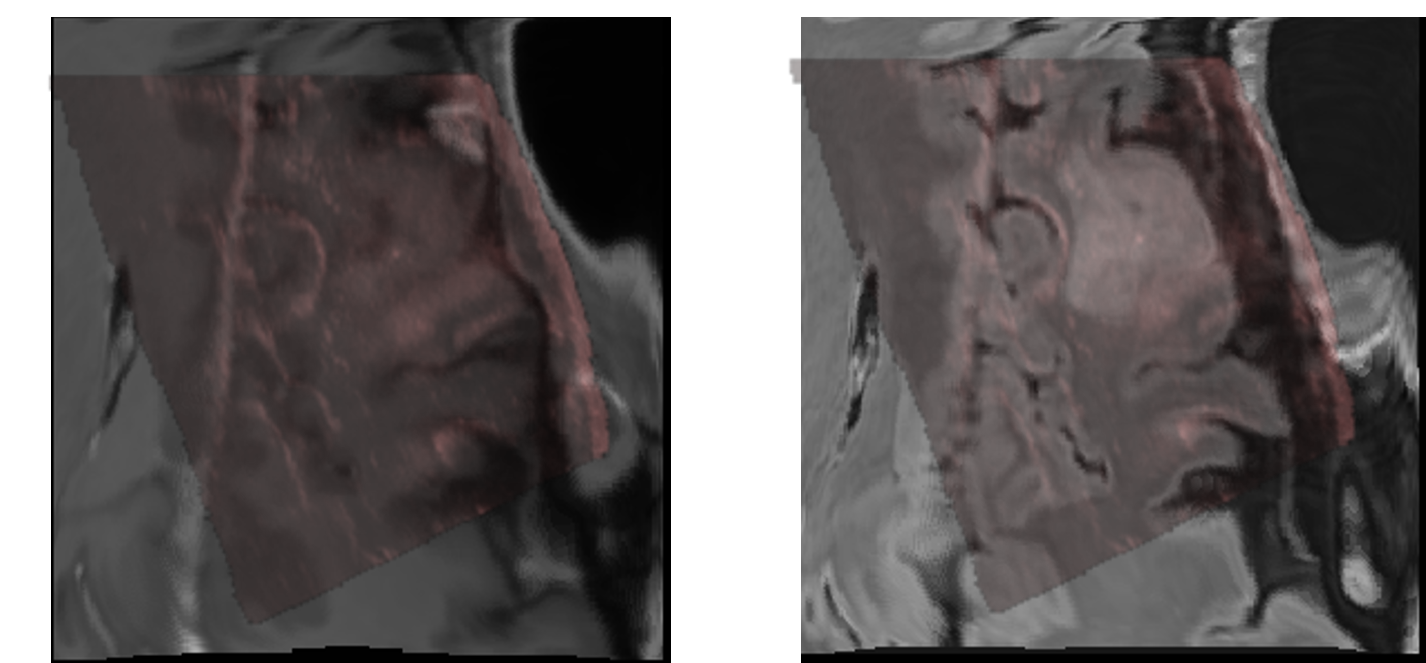

Since the ReMIND2Reg Sub-challenge includes only five patients (ten cases) with annotation information as the validation set with all exhibiting relatively small deformations, validation based solely on this dataset may lead to potential overfitting to a limited number of similar data, making it difficult to comprehensively evaluate the performance of the methods. Therefore, we conducted additional experiments on the Resect dataset, with results presented in Table 2. On this more diverse dataset, MCPO-deform achieved superior average TRE of 1.798 ±\pm 1.301 mm, while other methods often failed to handle cases with large deformations effectively. As illustrated in Fig. 3, which shows a case from the Resect dataset with an initial deformation of 19.731 mm, MCPO-deform successfully aligned key anatomical regions between the fixed and warped images. For this case, MCPO-deform achieved registration errors of 1.136 mm (FLAIR to ultrasound) and 1.368 mm (ceT1 to ultrasound). In comparison, MCPO-rigid only reached 13.313 mm and 16.195 mm, respectively. The visualization result for this case is shown in Fig. 4. Considering these results, we ultimately submitted MCPO-deform as the Docker for the testing phase of the ReMIND2Reg sub-challenge.

Refer to caption

Figure 3: Visualization results of a large deformation case in the Resect dataset using MCPO-deform.

Figure 4: Visualization result of MRI-US fusion for the large deformation case before (left) and after (right) registration using MCPO-deform.